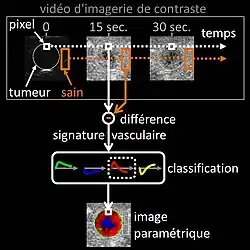

Échographie avec produit de contraste

L’échographie de contraste est celle qui utilise un produit de contraste[13]. Le produit de contraste composé de microbulles est injecté dans la circulation sanguine par voie intraveineuse au moment de l’examen échographique du patient. Tel que découvert par le docteur Raymond Gramiak en 1968[14], les microbulles du produit de contraste sont très réfléchissantes aux ultrasons pendant l'examen échographique; permettant ainsi d’imager la vascularisation sanguine des organes à des fins diagnostiques. Un usage clinique répandu de l'échographie de contraste est la détection de la tumeur métastatique dont la prise de contraste (évolution temporelle de la concentration du produit de contraste dans le sang) est plus rapide que celle du tissu biologique sain entourant la tumeur[15]. Il existe aussi des applications en échocardiographie de contraste[16] pour obtenir une meilleure délinéation de la paroi ventriculaire dans l’image échographique, constituant une aide supplémentaire dans l’évaluation du déficit contractile du cœur à la suite d'un infarctus du myocarde. Enfin, des applications en perfusion quantitative[17] (mesure relative du flux sanguin[18]) émergent pour le suivi thérapeutique pharmacologique du cancer, méthodologie élaborée par le docteur Nathalie Lassau en 2011[19] permettant d'identifier au plus tôt la réponse du patient au traitement anti-cancéreux afin d'orienter au mieux la conduite thérapeutique[20].

Parmi les techniques de l'échographie de contraste utilisées par les radiologues en pratique clinique, se distingue la méthode d’imagerie paramétrique des signatures vasculaires[21] inventée par le docteur Nicolas Rognin en 2010[22]. Cette méthode a été conçue comme un outil d’aide au diagnostic du cancer, facilitant la caractérisation d’une tumeur suspecte (définir si elle est bénigne ou maligne) dans un organe. D’un point de vue fonctionnel, la méthode analyse informatiquement[23],[24] une série temporelle d’images (enregistrement numérique vidéo en temps réel des images échographiques de contraste pendant l'examen). Deux étapes successives de traitement du signal sont appliquées à chaque pixel dans la tumeur, comme suit :

- calcul de la signature vasculaire (c'est-à-dire de la différence de prise de contraste avec le tissu sain entourant la tumeur) ;

- classification automatique de la signature vasculaire calculée en un paramètre, ce dernier prenant l'une des quatre couleurs suivantes :

- verte pour l'hypervascularisation continue (prise de contraste supérieure à celle du tissu sain),

- bleue pour l'hypovascularisation continue (prise de contraste inférieure à celle du tissu sain),

- rouge pour l'hypervascularisation rapide (prise de contraste avant celle du tissu sain) ou

- jaune pour l'hypovascularisation rapide (prise de contraste après celle du tissu sain).

Une fois le traitement du signal de chaque pixel de la tumeur terminé, la carte spatiale en couleur du paramètre est affichée sur l’écran d’un ordinateur ; synthétisant ainsi l’ensemble de l’information vasculaire en une seule et même image appelée « image paramétrique » (voir la dernière figure de l’article de presse[25] comme illustration d’images paramétriques en clinique). Cette image paramétrique est ensuite interprétée par le radiologue sur la base de la couleur prédominante dans la tumeur : le rouge indiquant une suspicion de malignité (risque de cancer), le vert ou le jaune une forte probabilité de bénignité. Dans le premier cas (suspicion de tumeur maligne), le radiologue prescrit une biopsie pour confirmer son diagnostic ou un scanner à rayons X pour une seconde opinion. Dans le deuxième cas (quasi-certitude de tumeur bénigne), seulement une surveillance dans les mois qui suivent est nécessaire avec un nouvel examen d’échographie de contraste. L’avantage clinique de la méthode d'imagerie paramétrique des signatures vasculaires consiste en ce qu'elle permet d'éviter la biopsie — procédure invasive risquée — systématique des tumeurs bénignes ou l'examen de scanner à rayons X exposant le patient à une dose d'irradiation. L’efficacité de la méthode a été évaluée positivement chez l’homme pour la caractérisation des tumeurs dans le foie[26]. Dans l'avenir la méthode pourrait être appliquée dans le cadre du dépistage du cancer de tout type d’organes, par exemple celui du sein[27] ou de la prostate).